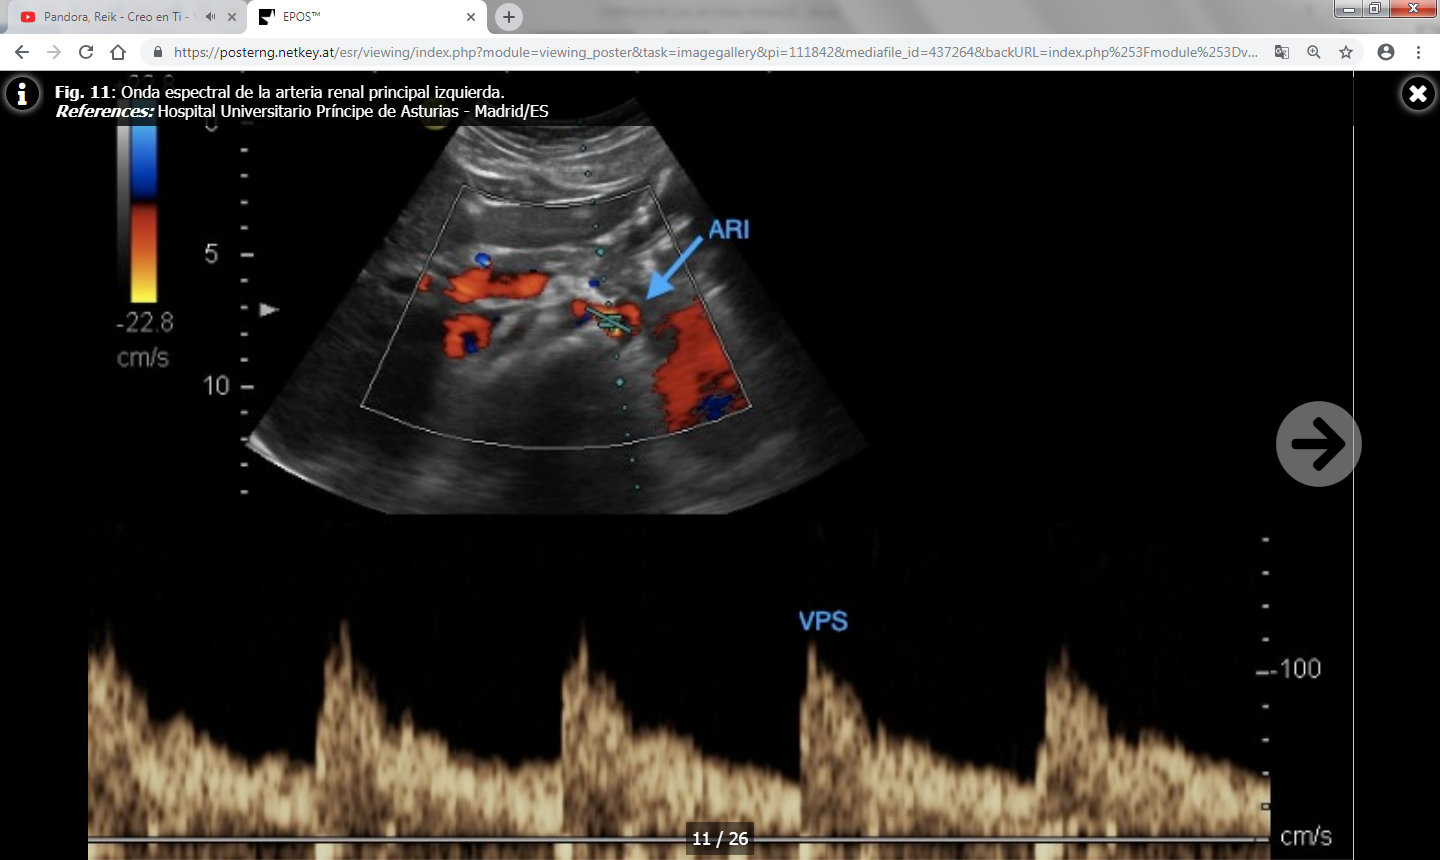

- Velocidad picosistólica (VPS) : Normal por debajo de 180-200 cm/s.

- Índice reno-aórtico (cociente entre la VPS de la arteria renal y la aorta): Normal por debajo de 3.5-3.6.

- Índice reno-renal (cociente entre la VPS en el punto de estenosis y en un punto distal a la misma): Normal por debajo de 4.